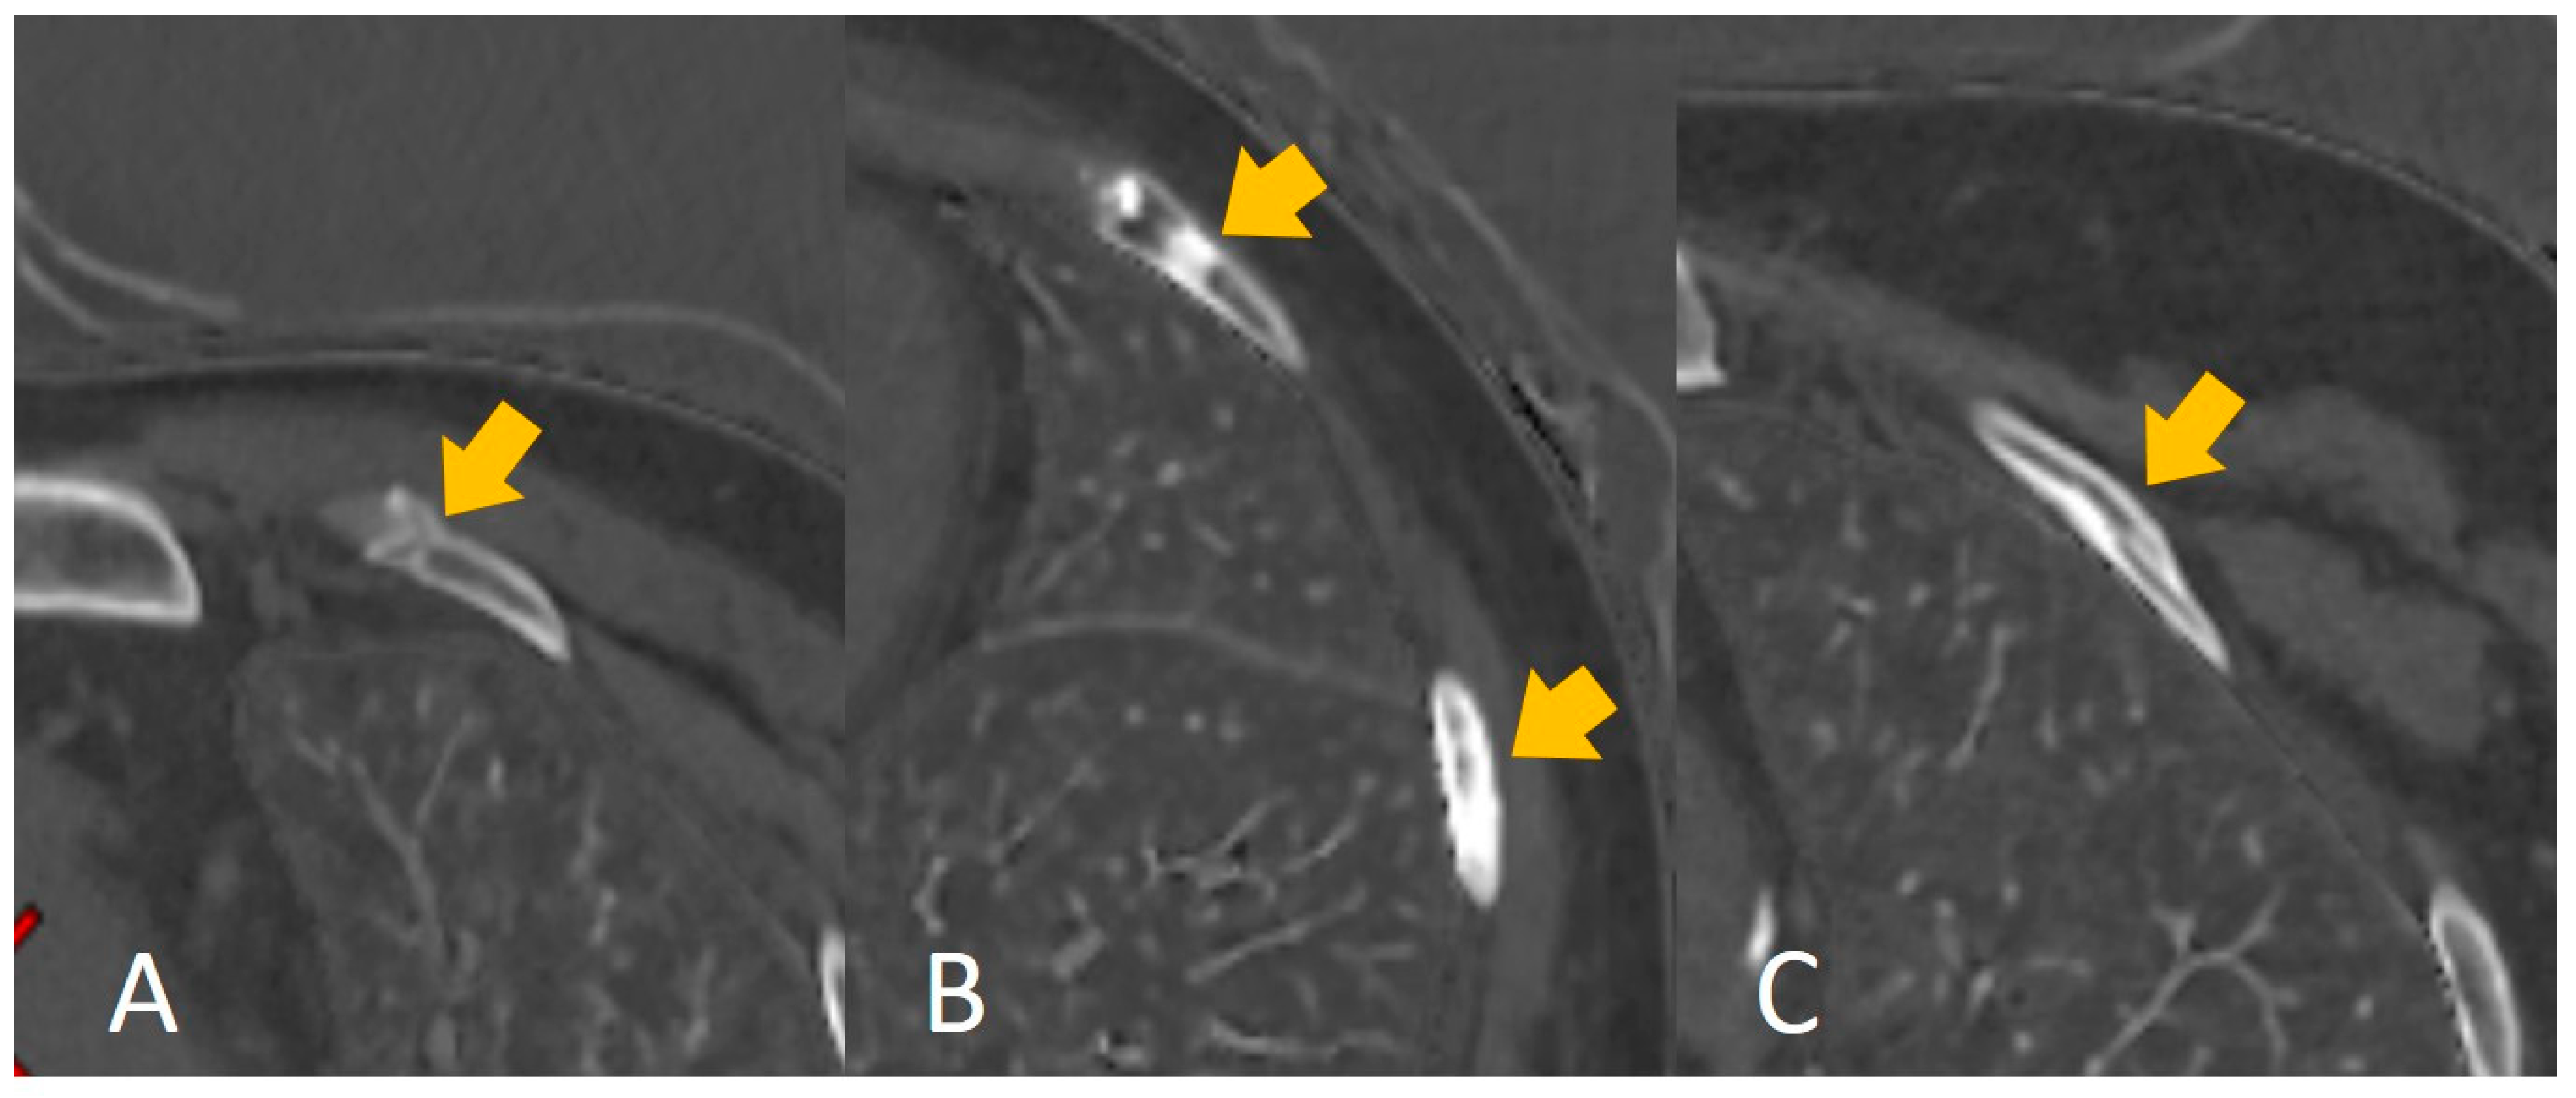

Rib fracture healing is affected by age [1,2], and evaluating the injury time of rib fractures from the imaging features of rib fractures is difficult even for an experienced radiologist (Figure 6), despite the existing knowledge (including morphological features) and experience. Our findings indicated and confirmed this phenomenon. First, the nine selected features (Table 1) correlated significantly with the grayscale. Machine learning showed better performance in distinguishing 30 days or 90 days (accuracy: 0.85 and 0.81, respectively) compared to the radiologists’ interpretation (0.74 and 0.71, respectively). Our results indicated machine learning could learn some features to help predict the injury time of rib fractures. Moreover, our results showed a better performance in distinguishing 30 days than 90 days in both machine learning and the radiologists’ interpretation; this may be explained by the natural characteristic of fracture healing. The less confusing imaging features of fracture healing within 30 days may make it easier to predict the injury time. However, an unsupervised radiomics-based model may not be superior to human performance despite the higher accuracy. Radiologists’ interpretation can be assisted by the prediction performance of the model; the increased accuracy of distinguishing 30 days and 90 days displayed effective complementarity following human–model collaboration, consistent with the results of previous artificial intelligence-based studies [17,19]. In the present study, we set the injury time of fresh fractures within 4 weeks (30 days). This could be attributed to the absence of an accepted clinical definition of fresh fractures [4] and the influence of age. Moreover, we set the injury time at 12 weeks (90 days) owing to the consensus of old fractures. For the rib fractures at 30 days, the imaging features principally comprised a sharp fracture line without periosteal reaction or callus formation, which was easily captured by the model or detected by human eyes. However, a comparison of the features up to 90 days, such as blurred edges of the fracture line with callus formation, mature callus, bone remodeling, and invisible features of the fracture line, added to the confounding factors for the evaluation. This finding may explain the better prediction of the injury time of rib fractures within 30 days. In the present study, we summarized the performance of other machine learning models (RF, LR, and GNB) in Supplementary File. Some models showed better performance than SVM in terms of overfitting, some models did not show satisfactory performance compared to SVM, and, finally, we chose SVM as the best model.

Figure 6.

The calcium-based material decomposition images: (A) shows the injury time of a rib fracture within 30 days; (B) shows the injury time of a rib fracture between 30 and 90 days, and (C) shows the injury time of a rib fracture over 90 days.